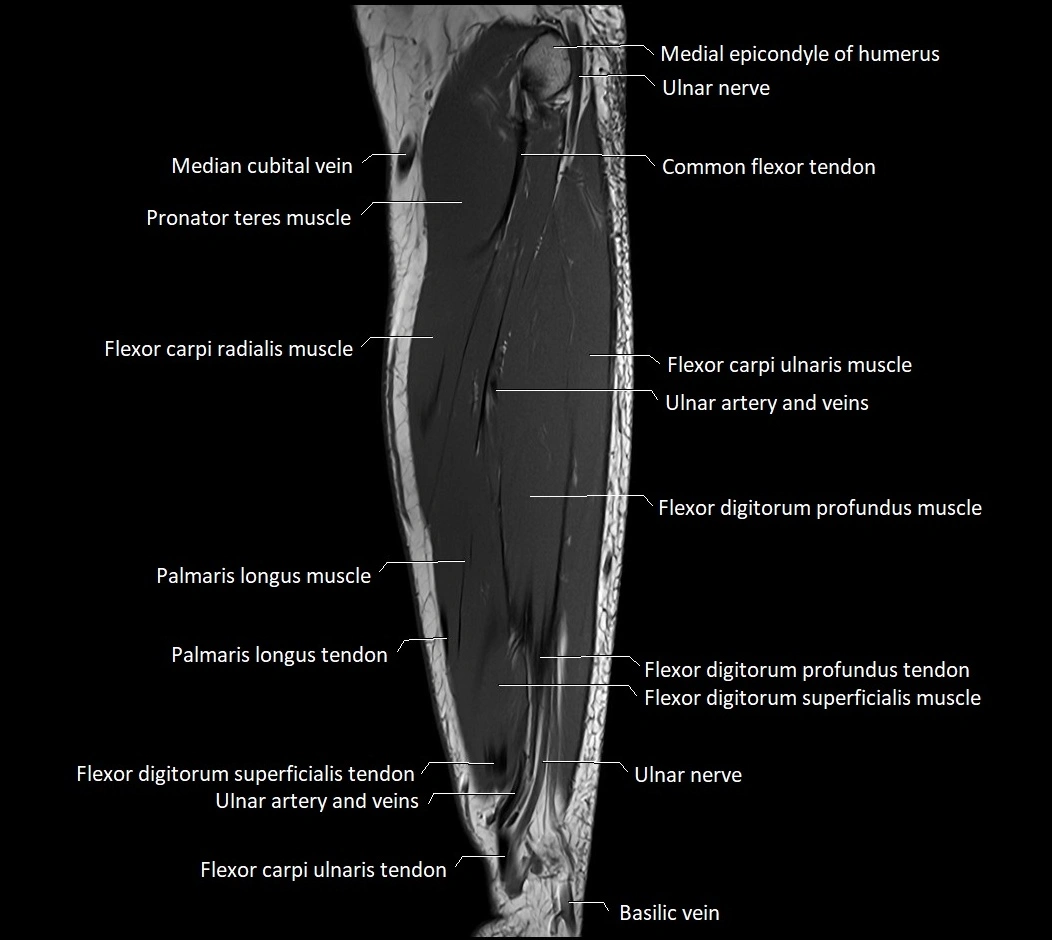

MRI images

image